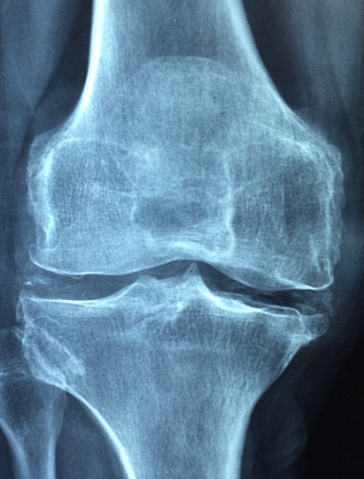

5. 관절 건강

물은 관절 내에서 연골에 영양을 공급하고 충격을 완화하는 역할을 합니다. 이는 관절 운동의 부담을 줄여 관절 건강을 지원합니다.